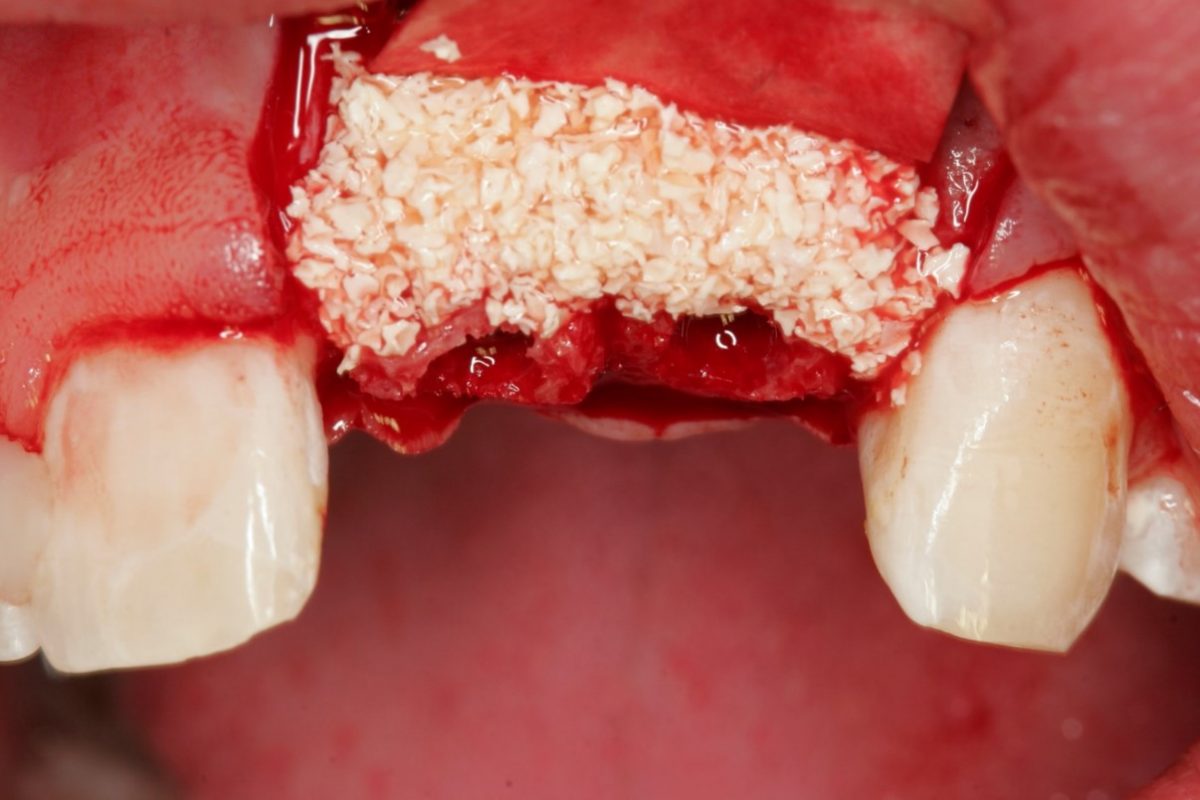

GBR with Jason membrane and cerabone

Dr. Filippo Fontana – Italy